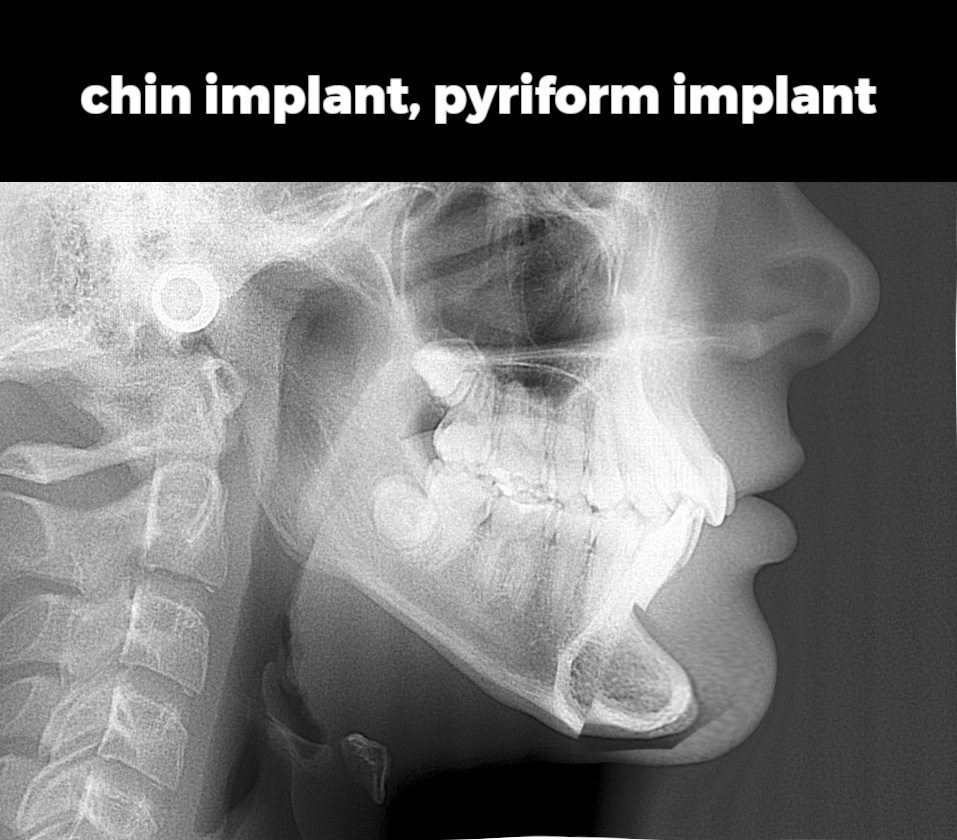

Pyriform or Paransal Implants (both address lower midface deficiency)

Some examples of people getting chin implants placed on downgrown jaws without first addressing chin rotation.

Chin implant: $2,000–$6,000 USD

Pyriform implant: $2,000–$6,000 USD

Pyriform or Paransal Implants (both address lower midface deficiency)

Some examples of people getting chin implants placed on downgrown jaws without first addressing chin rotation.

Chin implant: $2,000–$6,000 USD

Pyriform implant: $2,000–$6,000 USD